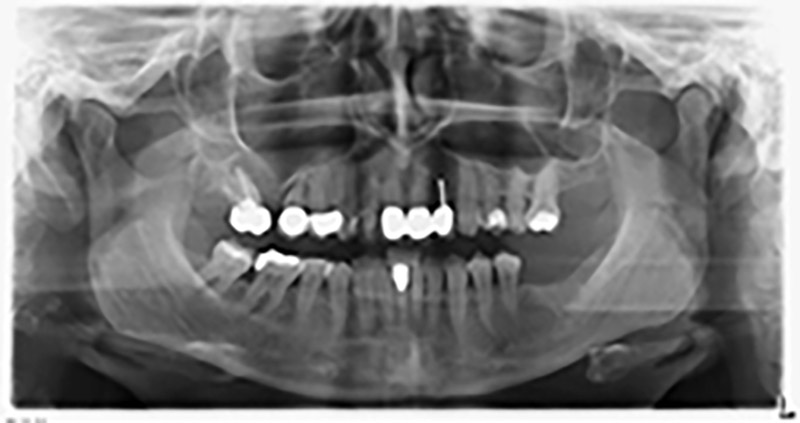

La paziente, 59 anni, presenta un caso di parodontite avanzata e descrive una sensazione di fastidio e scarsa sensibilità gustativa dal primo quadrante in direzione distale. L'esame clinico rivela tasche parodontali generalmente diffuse e un'atrofia ossea molto avanzata nelle regioni 16 e 14. L'esito è confermato dalla radiologia (fig. 1). Non è possibile salvare i denti 16 e 14.

Al fine di pianificare e minimizzare i rischi, circa sei mesi dopo l'estrazione dei denti 16 e 14 viene effettuata una tomografia digitale volumetrica (DVT, Planmeca), la quale conferma chiaramente la mancata rigenerazione ossea nel volume desiderato (da fig. 2 a 7).